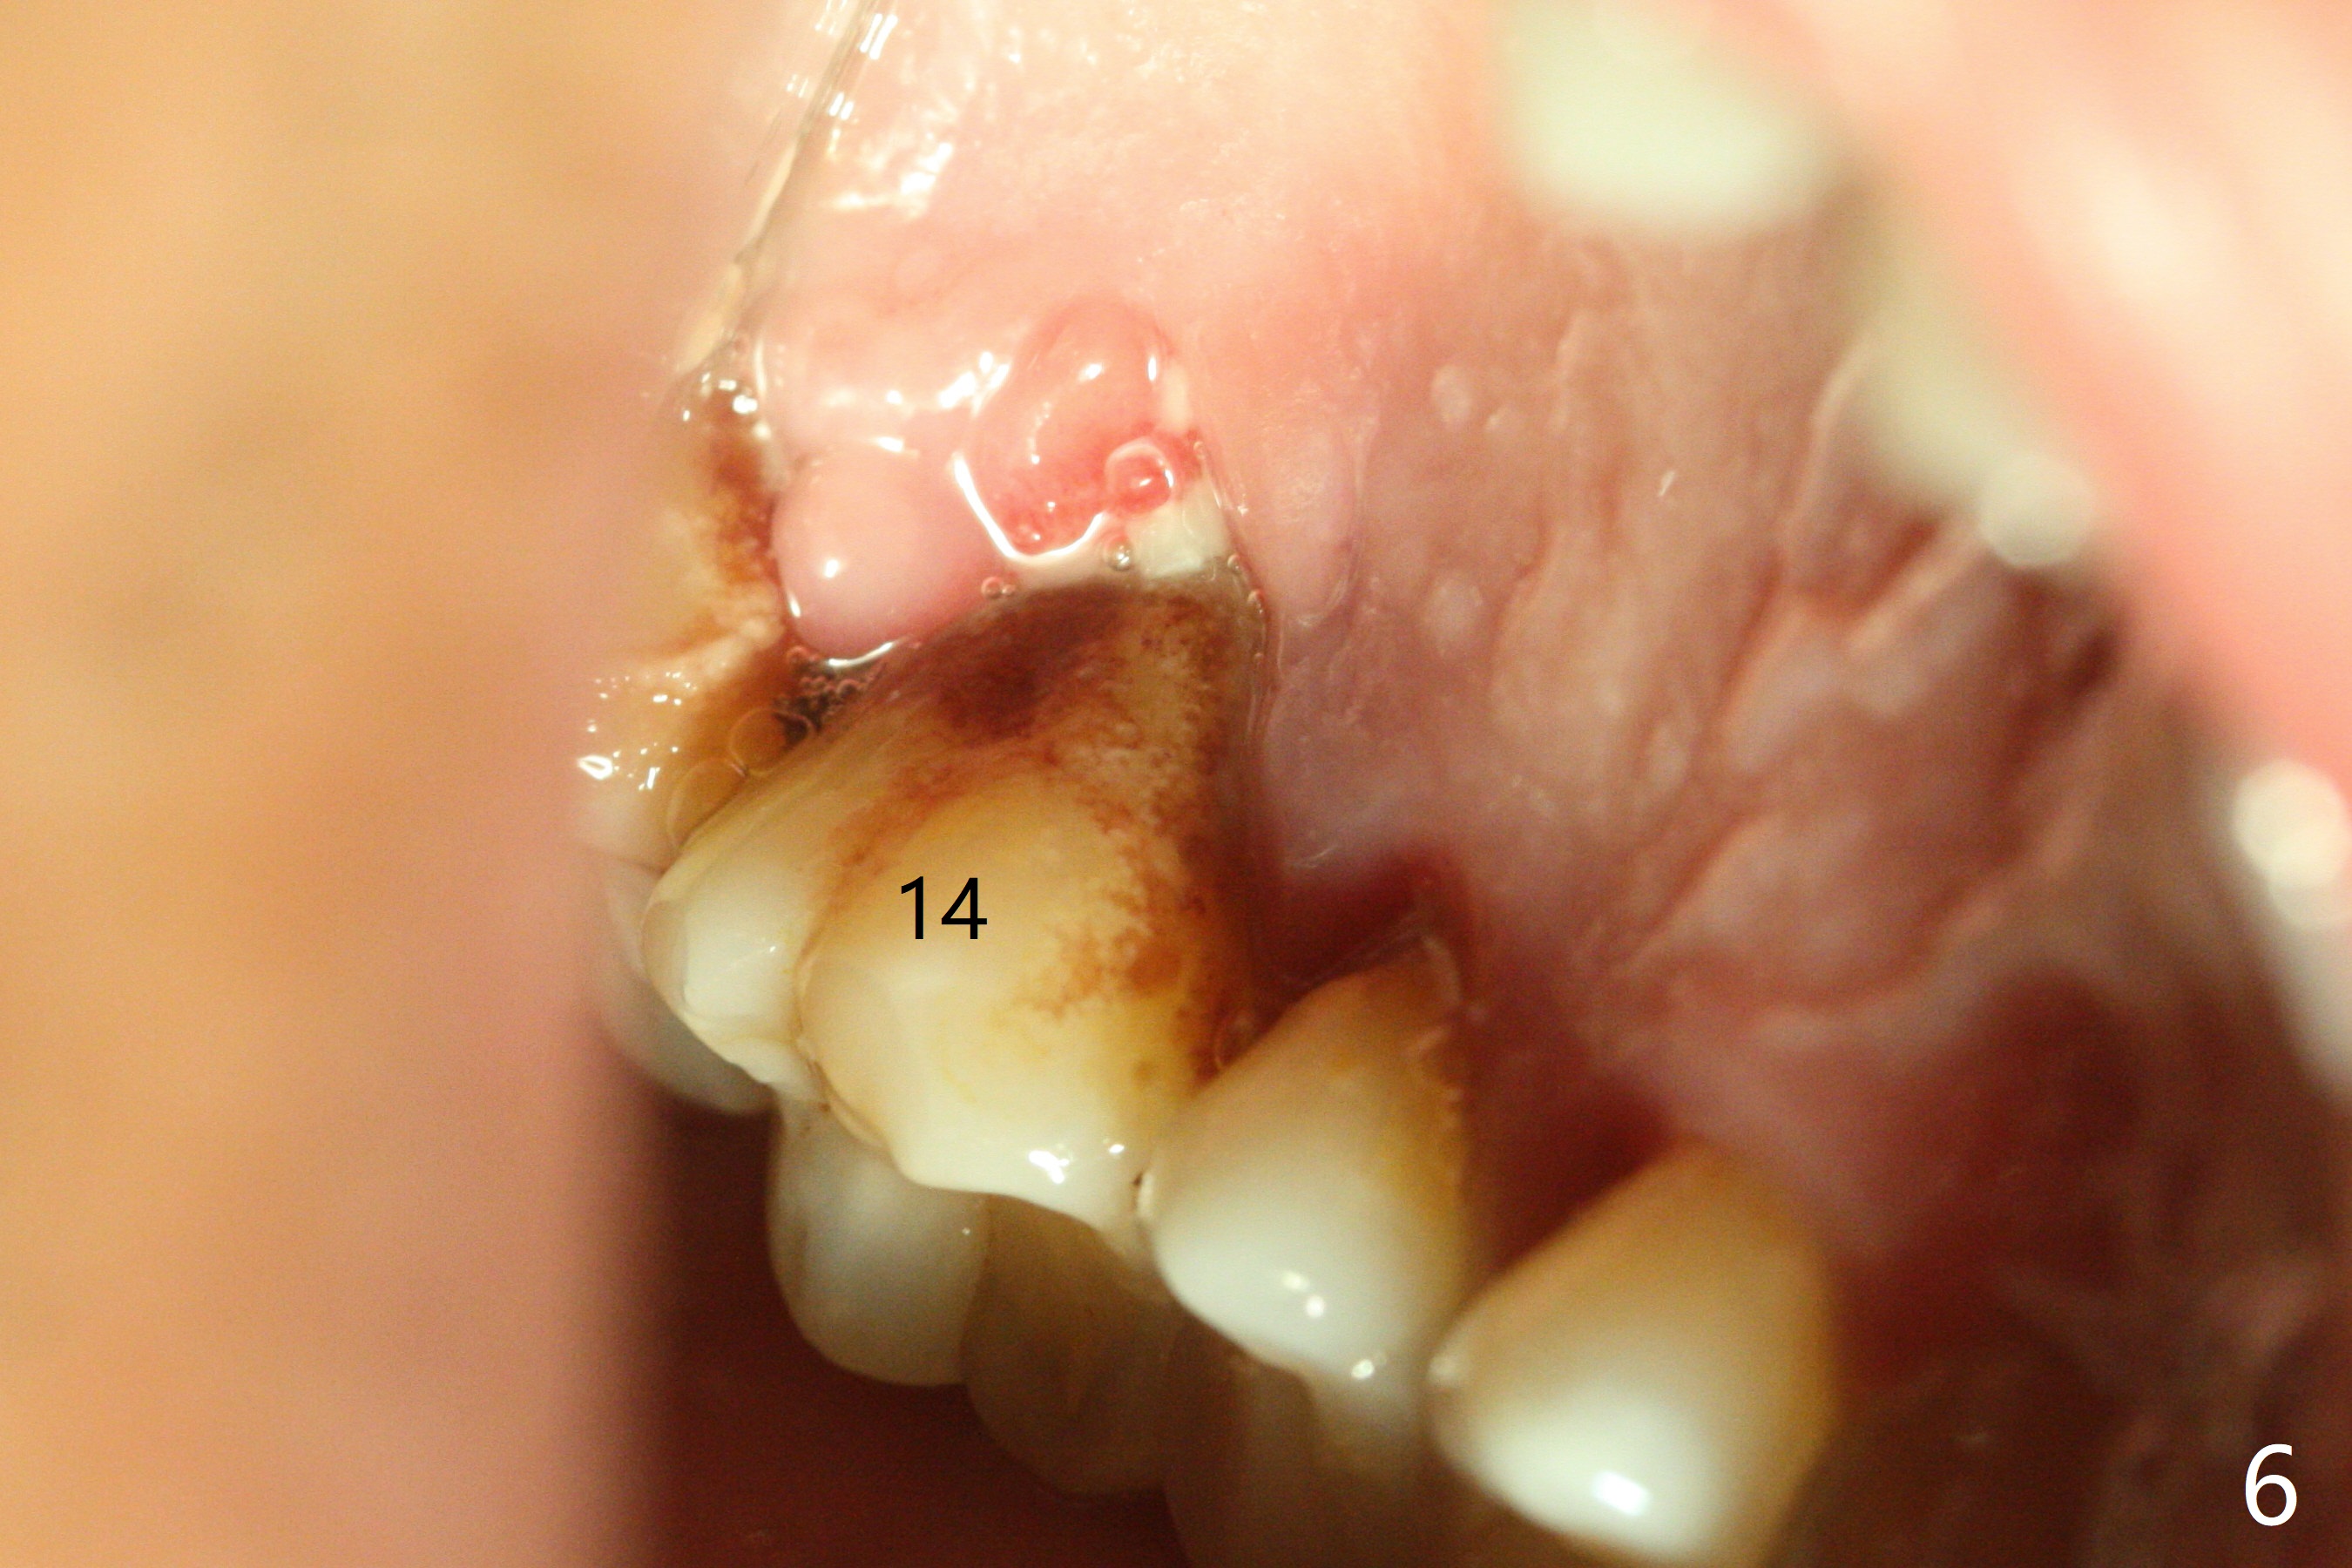

A 45-year-old man has chronic generalized moderate localized severe periodontitis; gingival recession is severe lingual of the tooth #14 with mobility II (Fig.1). The low bone density outline (Fig.1 white dashed line) is larger than the roots, suggesting lingual bone loss/low lingual crest. Although the bone height seems to be 11 mm (Fig.2), the bone responsible for primary stability of an implant will be apical (Fig.3 *,4). The implant platform will be ~3 mm subcrestal buccal, while ~3 mm supragingival lingual (Fig.5). The diameter of the implant will not be too large, 4.5 mm (dummy). There will be not biologic width issue. The large perimplant gap will be closed with sticky bone. Severe palatal gingival recession is shown pre- (Fig.6) and post- (Fig.7) SRP. #30 Gutta Percha inserted palatal reaches the highest point of the low bone density lesion (Fig.8). Pulpal test and CT will determine that endodontic treatment can regrow bone or that socket preservation is needed with Cytoplast.